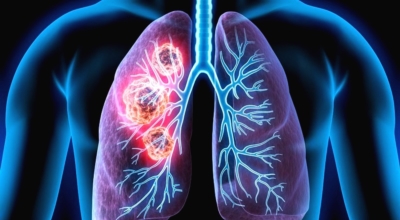

인체가 순조롭게 기능을 발휘하려면 폐 건강이 필수다. 폐는 인체가 효율적으로 움직이는 데 있어 바퀴 안에 있는 톱니 같은 역할을 하기 때문이예요. 산소를 제공하는 폐 기능이 감소하게되면 폐렴이나, 만성 폐쇄성 폐질환(COPD), 천식 등 정도가 심한 호흡기 질환 발생 위험이 증가해요. 이런 질병들은 폐를 공격해 숨쉬기 힘들게 만들어요.

특별히 현대 사회에서 폐는 가장 시달리는 장기 중 한 종류다. 가지가지 공해 성분으로 오염된 공기에 미세 먼지, 황사까지 더하면 폐 안쪽에 있는 허파꽈리(폐포)부터 정도가 심한 훼손을 입습니다. 따라서 폐 건강을 증진시키기 위하여는 폐에 좋은 음식을 섭취할 필요가 있어요.